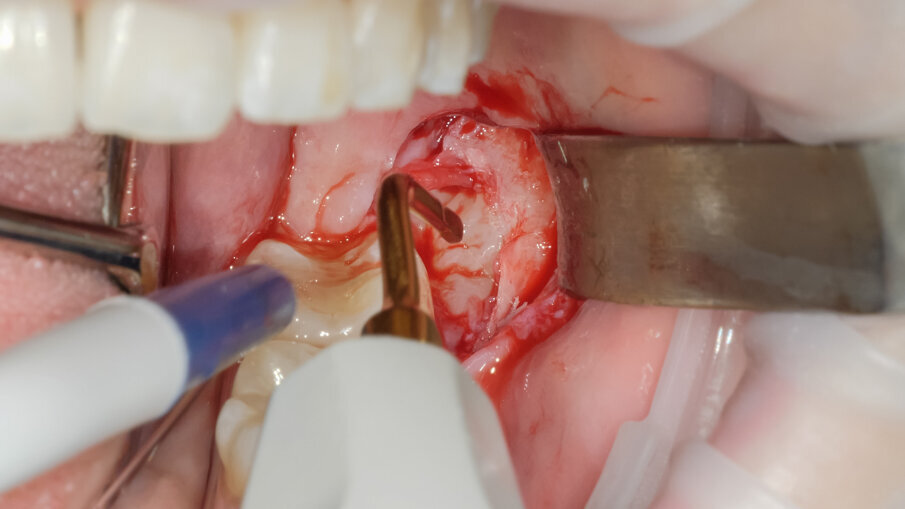

La scelta condivisa è quella di utilizzare la tecnologia piezolettrica per le fasi di odontotomia, solo nelle zone di difficile accesso o in prossimità di strutture anatomiche a rischio come il nervo alveolare inferiore. Per la fase di lussazione si è applicato il protocollo descritto da Fontanella utilizzando il nuovo inserto EXL1 (Figg. 6, 7). Questo inserto insieme agli altri due inserti lussativi (EXL2, EXL3) hanno la particolarità di sfruttare l’impulso piezoelettrico associato al movimento lussativo dell’inserto montato sul manipolo. La cavità residua è stata gestita rimuovendo i residui di sacco follicolare e detergendo il sito post estrattivo sfruttando l’effetto cavitazionale della tecnologia piezoelettirca (Fig. 8). Il lembo riposizionato è stato suturato con chiusura per prima intenzione con punti singoli riassorbibili 4/0 (Fig. 9). Al controllo post operatorio la ferita presentava una guarigione nella norma, e la paziente riferiva un post operatorio senza particolare gonfiore e con assunzione di antidolorifico solo nel primo giorno post chirurgico